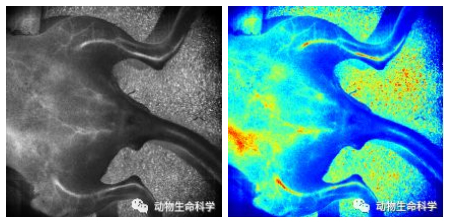

超高2K分辨率(2048 × 2048)

带你清晰观察肠系膜第五分支血管

2-肠系膜第五分支血管.jpg

肠系膜

同时展示

实物图、散斑图、伪彩图

互为参照,同步调整